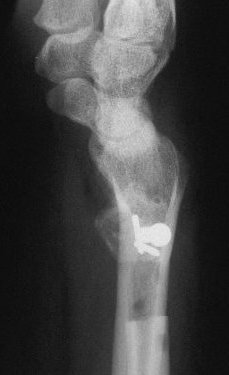

Case 2. Minimal Madelungs picture following pediatric distal radius fracture.